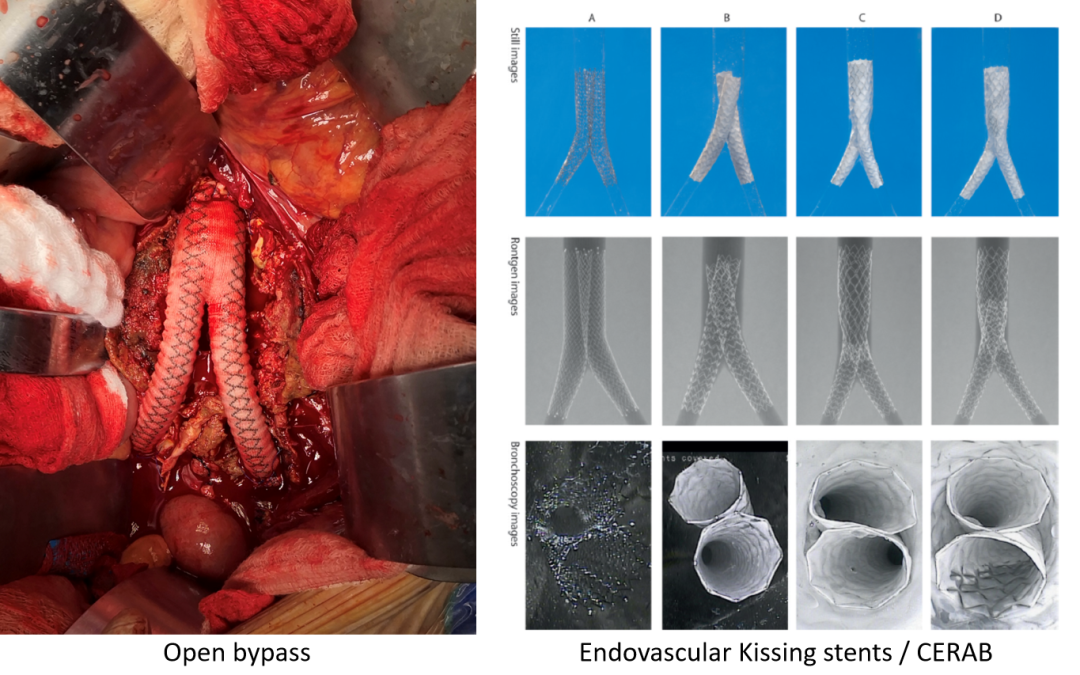

开放旁路手术:如主-双股动脉旁路(ABF),是传统经典术式;

腔内技术:包括对吻支架(Kissing stents)和 CERAB 技术;

CERAB技术

通过覆膜支架重建主动脉分叉治疗主髂动脉病变。

开放旁路手术,腔内对吻支架和CERAB技术是目前治疗主髂动脉闭塞的主要方法